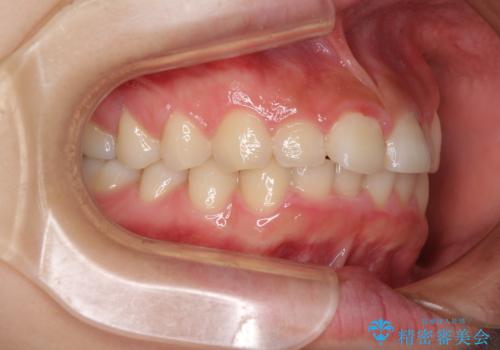

前歯のデコボコと突出感 インビザラインによる矯正治療

- 上下前歯のデコボコと、上顎前歯の突出感を気にして来院された患者様です。

インビザラインによる上下歯列の側方拡大と後方移動、IPR(歯と歯の間を削る)にるスペースの獲得により歯列を整えることとしました。

毎日22時間以上しっかりとマウスピースを装着していただいたので、スムーズに治療が進みました。歯と歯の間を削ることでうまくスペースコントロールでき、1年強で終えることができました。